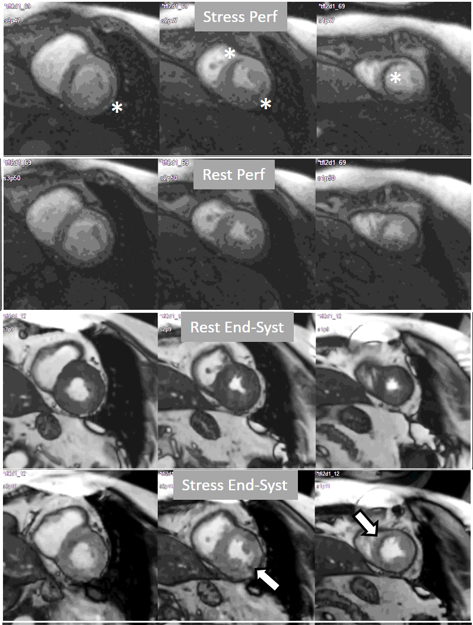

A study exploring further components of perfusion defects [36] showed that, besides extension and transmurality, also the presence of inducible contractile defect and, particularly, persistence of the defect throughout the full duration of the sequence, were also related with an adverse prognosis (Fig. 21). High values of an ischemic burden score based on these parameters showed prognostic value for clinical improvement after PCI in patients with chronic total coronary occlusion [48].

Fig. 21.Grading perfusion defects. The upper 2 panels present with the very last frames of perfusion studies where a persistent defect is seen at stress in the infero-lateral and antero-septal regions (asterisks). The lower 2 panels show corresponding end-systolic frames with conspicuous contractile adenosine-induced defects (arrows) in both regions.